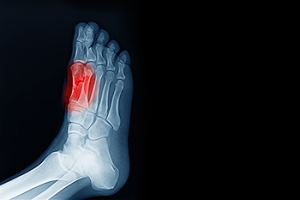

What Is Sesamoiditis?

Sesamoiditis is the inflammation of two small sesamoid bones located beneath the big toe joint. It is often caused by repetitive stress, high impact activities, or wearing ill-fitting shoes. Athletes, dancers, and anyone who spend long periods on their feet are at a higher risk. Symptoms include pain and swelling under the ball of the foot, difficulty bending the big toe, and discomfort when walking or running. A podiatrist can provide a thorough evaluation, recommend custom orthotics, prescribe anti-inflammatory treatments, and develop a stretching and strengthening program to relieve pain and prevent recurrence. Early intervention is important for a successful recovery. If you have pain in this part of your foot, it is suggested that you consult a podiatrist to receive expert care and get back to pain-free movement.

Sesamoiditis is a condition of the foot that affects the ball of the foot. It is more common in younger people than it is in older people. It can also occur with people who have begun a new exercise program, since their bodies are adjusting to the new physical regimen. Pain may also be caused by the inflammation of tendons surrounding the bones. It is important to seek treatment in its early stages because if you ignore the pain, this condition can lead to more serious problems such as severe irritation and bone fractures.

Sesamoiditis

Sesamoiditis is a condition that affects the joint that is just behind the big toe in the area known as the ball of the foot. It is most common in younger people and people who have just begun an exercise program. Since the sesamoid bones are like a pulley controlling the big toe, they can rub against each other and cause a gradual onset of pain. Pain may also be caused by the inflammation of tendons surrounding the bones. If ignored, sesamoiditis can lead to other, more serious problems such as severe irritation and fractures of the bones.

The cause of sesamoiditis is sudden increase in activity. The ball of your foot acts as a springboard to help you lift off when you are jogging or running. Sudden increase in the use of these bones or the tendon that controls them can cause irritation. The tendon then begins to develop inflammation and the joint begins to swell. People with smaller, bonier feet or those with a high arch are typically more susceptible to this condition.

Sesamoiditis is fairly simple to diagnose since the symptoms have a gradual onset rather than a sudden impact. The symptoms begin with slight irritation around the joint shortly after the increase in activity. The discomfort eventually turns to pain with light swelling and possibly redness. Although redness or bruising are rare, this may be a symptom. After each session of exercising, the aggravated joint becomes more irritated and increases into a very intense throbbing.

Treatment for sesamoiditis can vary depending on the severity of the situation. However, treatment is almost always approached in a noninvasive way. For a case that is just beginning the doctor may recommend a very strict rest period that will limit the activity allowed on the joint. If you must be active, a recommendation for as modified shoe or insole, along with bandaging and immobilizing the big toe will be made to ensure that pressure is not placed on the joint. For severe cases, it is typically recommended that the joint and the big toe be completely immobilized to allow adequate time to heal. Ice and an over the counter anti-inflammatory may can help with the pain and discomfort while you are at rest.